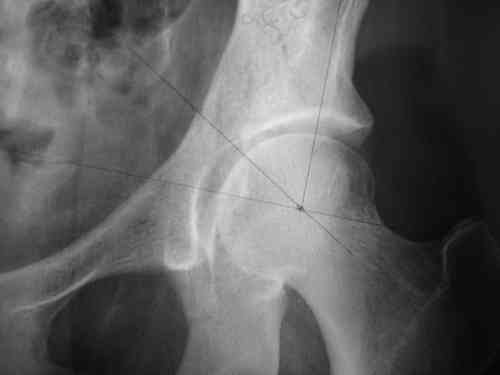

прилагаю пример с такой же давностью травмы, репонировали аппаратом

> в аппарате или одномоментно открыто. Лично я склоняюсь к аппаратному лечению на первом этапе.

задача непростая, если мало опыта в этом деле, подумайте еще раз